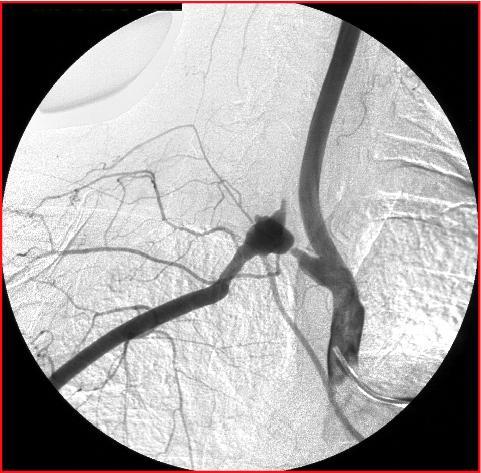

Patient avec endocardite infectieuse: qu’est ce que c’est? quel mécanisme?

Anévrisme mycotique; mécanisme immunologique